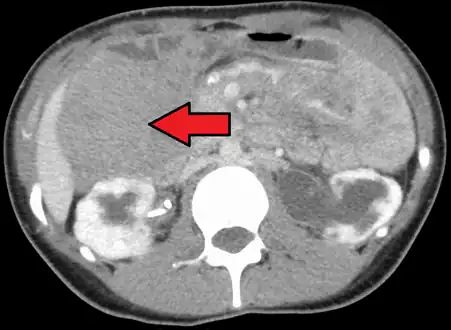

| Desmoid tumor as seen on CT scan | |

Aggressive fibromatosis or desmoid tumor is a rare condition. Desmoid tumors arise from cells called fibroblasts, which are found throughout the body and provide structural support, protection to the vital organs, and play a critical role in wound healing. These tumors tend to occur in women in their thirties, but can occur in anyone at any age. They can be either relatively slow-growing or malignant. However, aggressive fibromatosis is locally aggressive and can cause life-threatening problems or even death when they compress vital organs such as intestines, kidneys, lungs, blood vessels, or nerves. Most cases are sporadic, but some are associated with familial adenomatous polyposis (FAP). Approximately 10% of individuals with Gardner's syndrome, a type of FAP with extracolonic features, have desmoid tumors.[1]